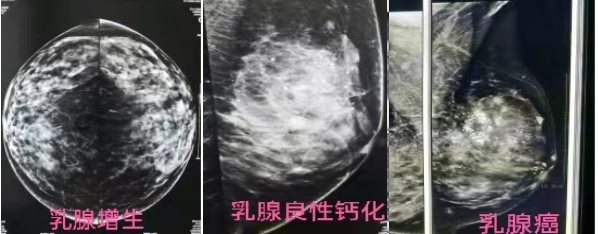

钼靶读音是(mù bǎ),钼靶就是乳腺钼靶,全称乳腺钼靶X线摄影检查,又称钼靶检查。钼靶检查是目前诊断乳腺疾病的首选和最可靠的无创性检测手段,痛苦相对较小,且分辨率高,留取的图像可供前后对比,目前已作为常规乳腺病的检查。

乳腺B超和钼靶是乳腺疾病筛查的两个常用检查方法,主要区别在于两者的成像原理不同。乳腺B超是利用超声波对乳腺的病变进行检查,钼靶是利用X线对乳腺的病变进行检查,通常两种检查方式是互补而不可替代的。乳腺彩超相对于年轻的女性来说是比较适合的,因为年轻女性乳腺都是多腺体型,在进行彩超检查时,可以看到小于1CM的微小结节。钼靶在查看钙化点方面,对诊断那些发生在导管内还没有形成明显结节的早期乳腺癌的诊断有绝对的优势,所以两者各有优势,相辅相成。